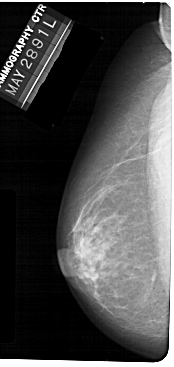

A_1304_1.RIGHT_MLO

RIGHT_MLO LINES 5491 PIXELS_PER_LINE 2611 BITS_PER_PIXEL 12 RESOLUTION 43.5 OVERLAY